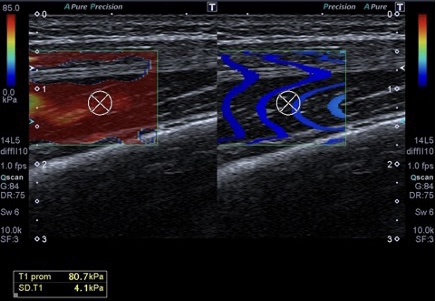

357. Kilopascales (kPc) en Elastrografía. Lo que el TSID debe saber.

Cuando hablamos de medicina moderna, las tecnologías de imagen han revolucionado la forma en que diagnosticamos y tratamos una variedad de enfermedades. Entre estas tecnologías se encuentra la elastografía, un método no invasivo para evaluar la rigidez de los tejidos internos del cuerpo. Pero, ¿alguna vez te has preguntado cómo se mide esta rigidez? Aquí es donde entran en juego los kilopascales (kPa). En este post, exploraremos qué son los kilopascales, su importancia en la elastografía y cómo se utilizan en la práctica médica.

La Importancia de los Kilopascales en Elastografía

La elastografía es una técnica que mide la rigidez o elasticidad de los tejidos blandos, como el hígado, los músculos y otros órganos. Esta técnica es especialmente valiosa para detectar cambios en la rigidez del tejido que podrían indicar condiciones médicas como fibrosis, cirrosis o tumores. En el ámbito de la elastografía, las medidas de rigidez se expresan típicamente en kilopascales.

• Evaluación Musculoesquelética: Utilizado en ortopedia para evaluar la rigidez de músculos y tendones.

En Tejidos Musculares Principales

La rigidez de los músculos puede variar, pero generalmente son más duros (mayor rigidez medida en kPa) cuando están contraídos y más blandos cuando están relajados.